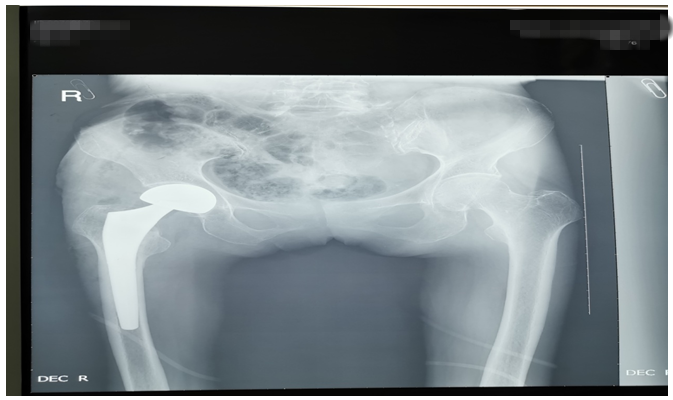

還有一位76歲鄧大媽,外傷致右側(cè)股骨頸骨折。外傷后因疫情鄧大媽一直未就診,在家非常痛苦,因疼痛不能平臥,一直坐位,臀部褥瘡形成,同時被骨折疼痛折磨地夜不能睡、不思飲食。鄧大媽基礎(chǔ)病較多,有高血壓病、腦梗塞、心臟病等病史,因骨折后時間長、錯位明顯,入院后積極治療內(nèi)科疾病,完善各項輔助檢查,在麻醉師及內(nèi)科醫(yī)師協(xié)助下,為鄧大媽成功行右側(cè)髖置換術(shù),手術(shù)順利。術(shù)后鄧大媽的臉上又有了笑容,夜間也能休息好了,術(shù)后第二天就開始下床活動,家屬看到自己的老母親恢復(fù)地這么好,非常滿意。(見下圖)

右髖正側(cè)位手術(shù)前后對比圖